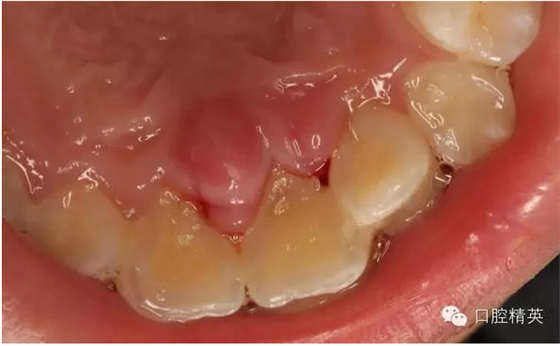

圖1.術(shù)前患者口內(nèi)像、牙槽窩輕度收縮、血凝塊穩(wěn)定、無(wú)滲出。

圖1.一周后復(fù)診拆線、唇側(cè)齦乳頭水腫。

圖2.拆線前腭側(cè)觀

圖3.拆線后唇側(cè)觀,牙齦乳頭輕度水腫

圖4.腭側(cè)觀21齦乳頭水腫明顯